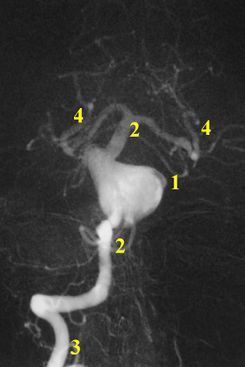

A cerebral angiogram from the same case as the CT scan above. It shows a large aneurysm (1) at the basilar artery (2). The basilar artery arises from the vertebral artery (3), into which radiocontrast was injected. Further along its course, the basilar artery splits into the two posterior cerebral arteries (4) that are part of the circle of Willis.